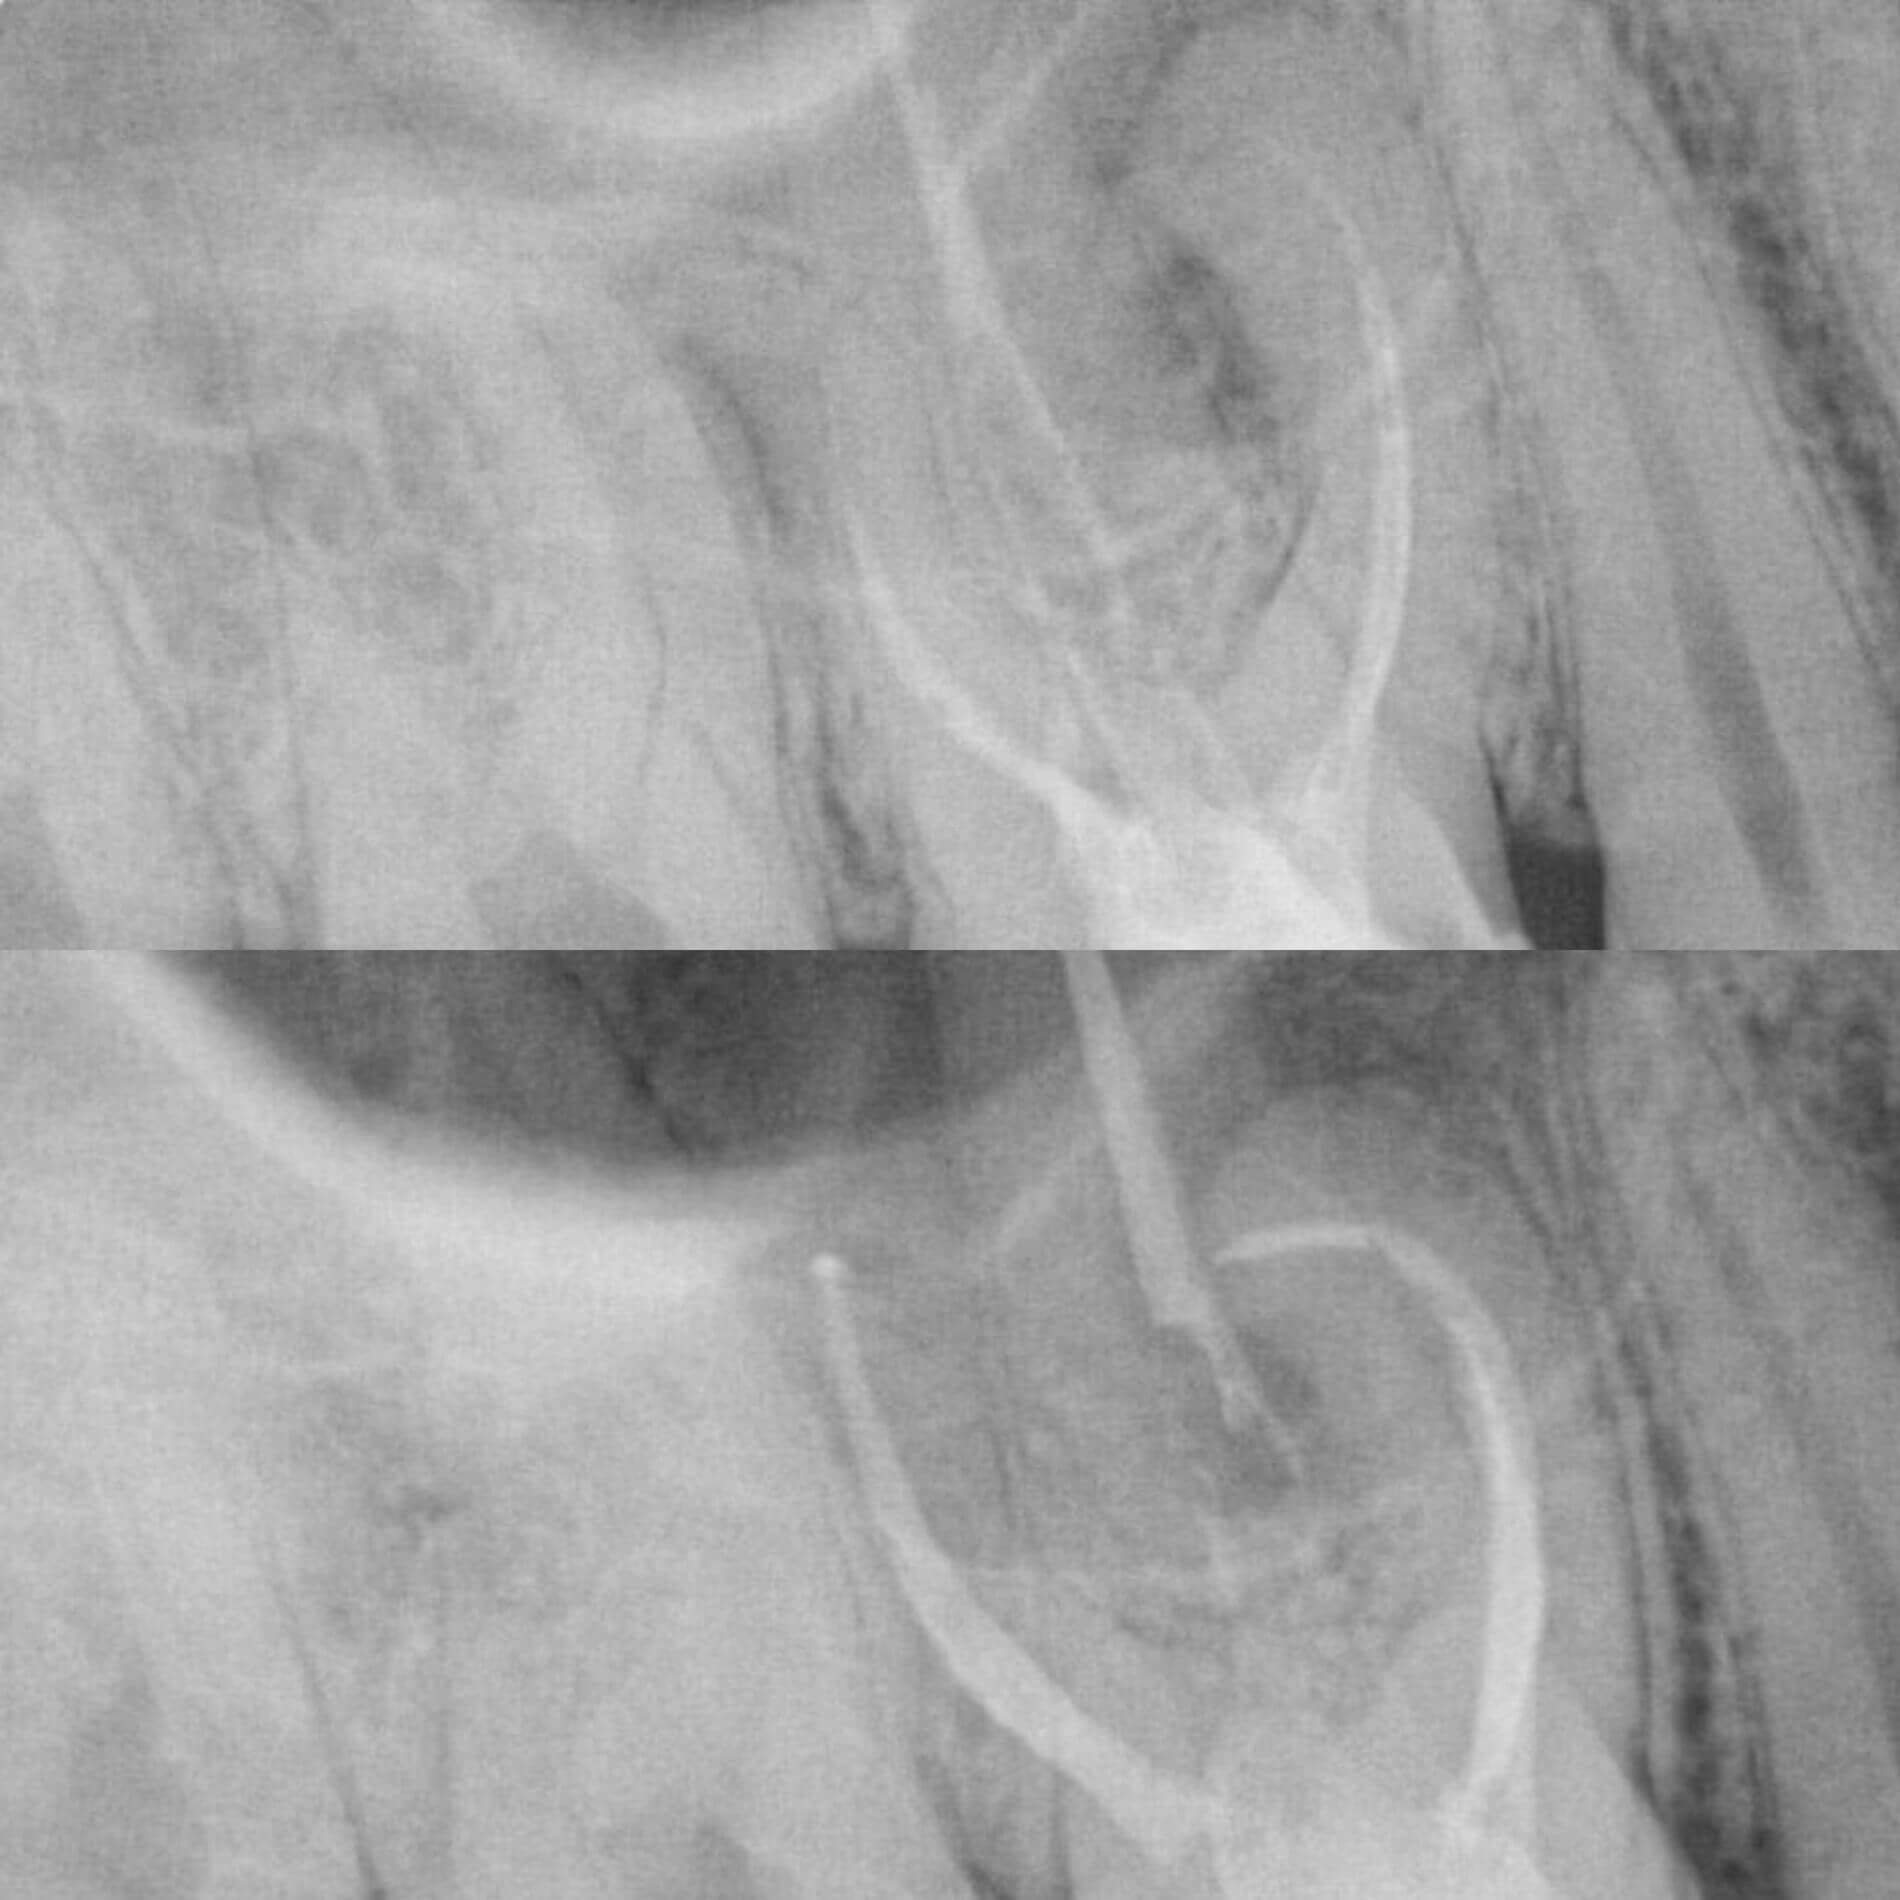

Мы уже говорили, качественное лечение зубных каналов – это довольно сложный и трудоемкий процесс, но с ним с легкостью справится наша космическая команда. Эта процедура затруднена отсутствием полноценного доступа к операционной полости, да еще зубные каналы часто искривлены и очень узкие, что делает невозможным визуальный контроль за проведением процедуры.

Но инновационные технологии и применение рентгенологического контроля выводят лечение каналов зуба во Львове специалистами Космической стоматологии Драганчука на новый межгалактический уровень.

Чтобы провести процедуру лечения и пломбирования каналов, мы в космической стоматологии Драганчука используем оптическое увеличение с помощью микроскопа Carl Zeisse.

Он позволяет вывести изображение на большой экран и масштабировать его, чтобы наша космическая команда могла осуществить все необходимые манипуляции особенно скрупулезно. Благодаря такому оптическому контролю каждого этапа лечения, мы можем оценить его эффективность и предотвратить возникновение осложнений.